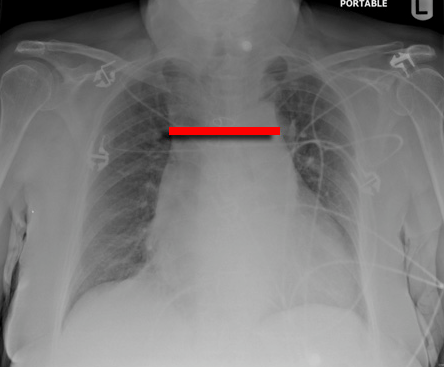

・胸部単純レントゲンで縦隔陰影の拡大(縦隔拡大>8cm)

(臥位では上縦隔は生理的に増大してしまうので判別困難。その場合は気管分岐部レベルでの椎体中央と大動脈陰影左縁の距離が5cm以上であれば縦隔拡大陽性とする。気管分岐部レベルでは臥位でも立位でも椎体中央と大動脈陰影左縁の距離は変わらないため)

縦隔の拡大の一例

縦隔拡大の一例その2